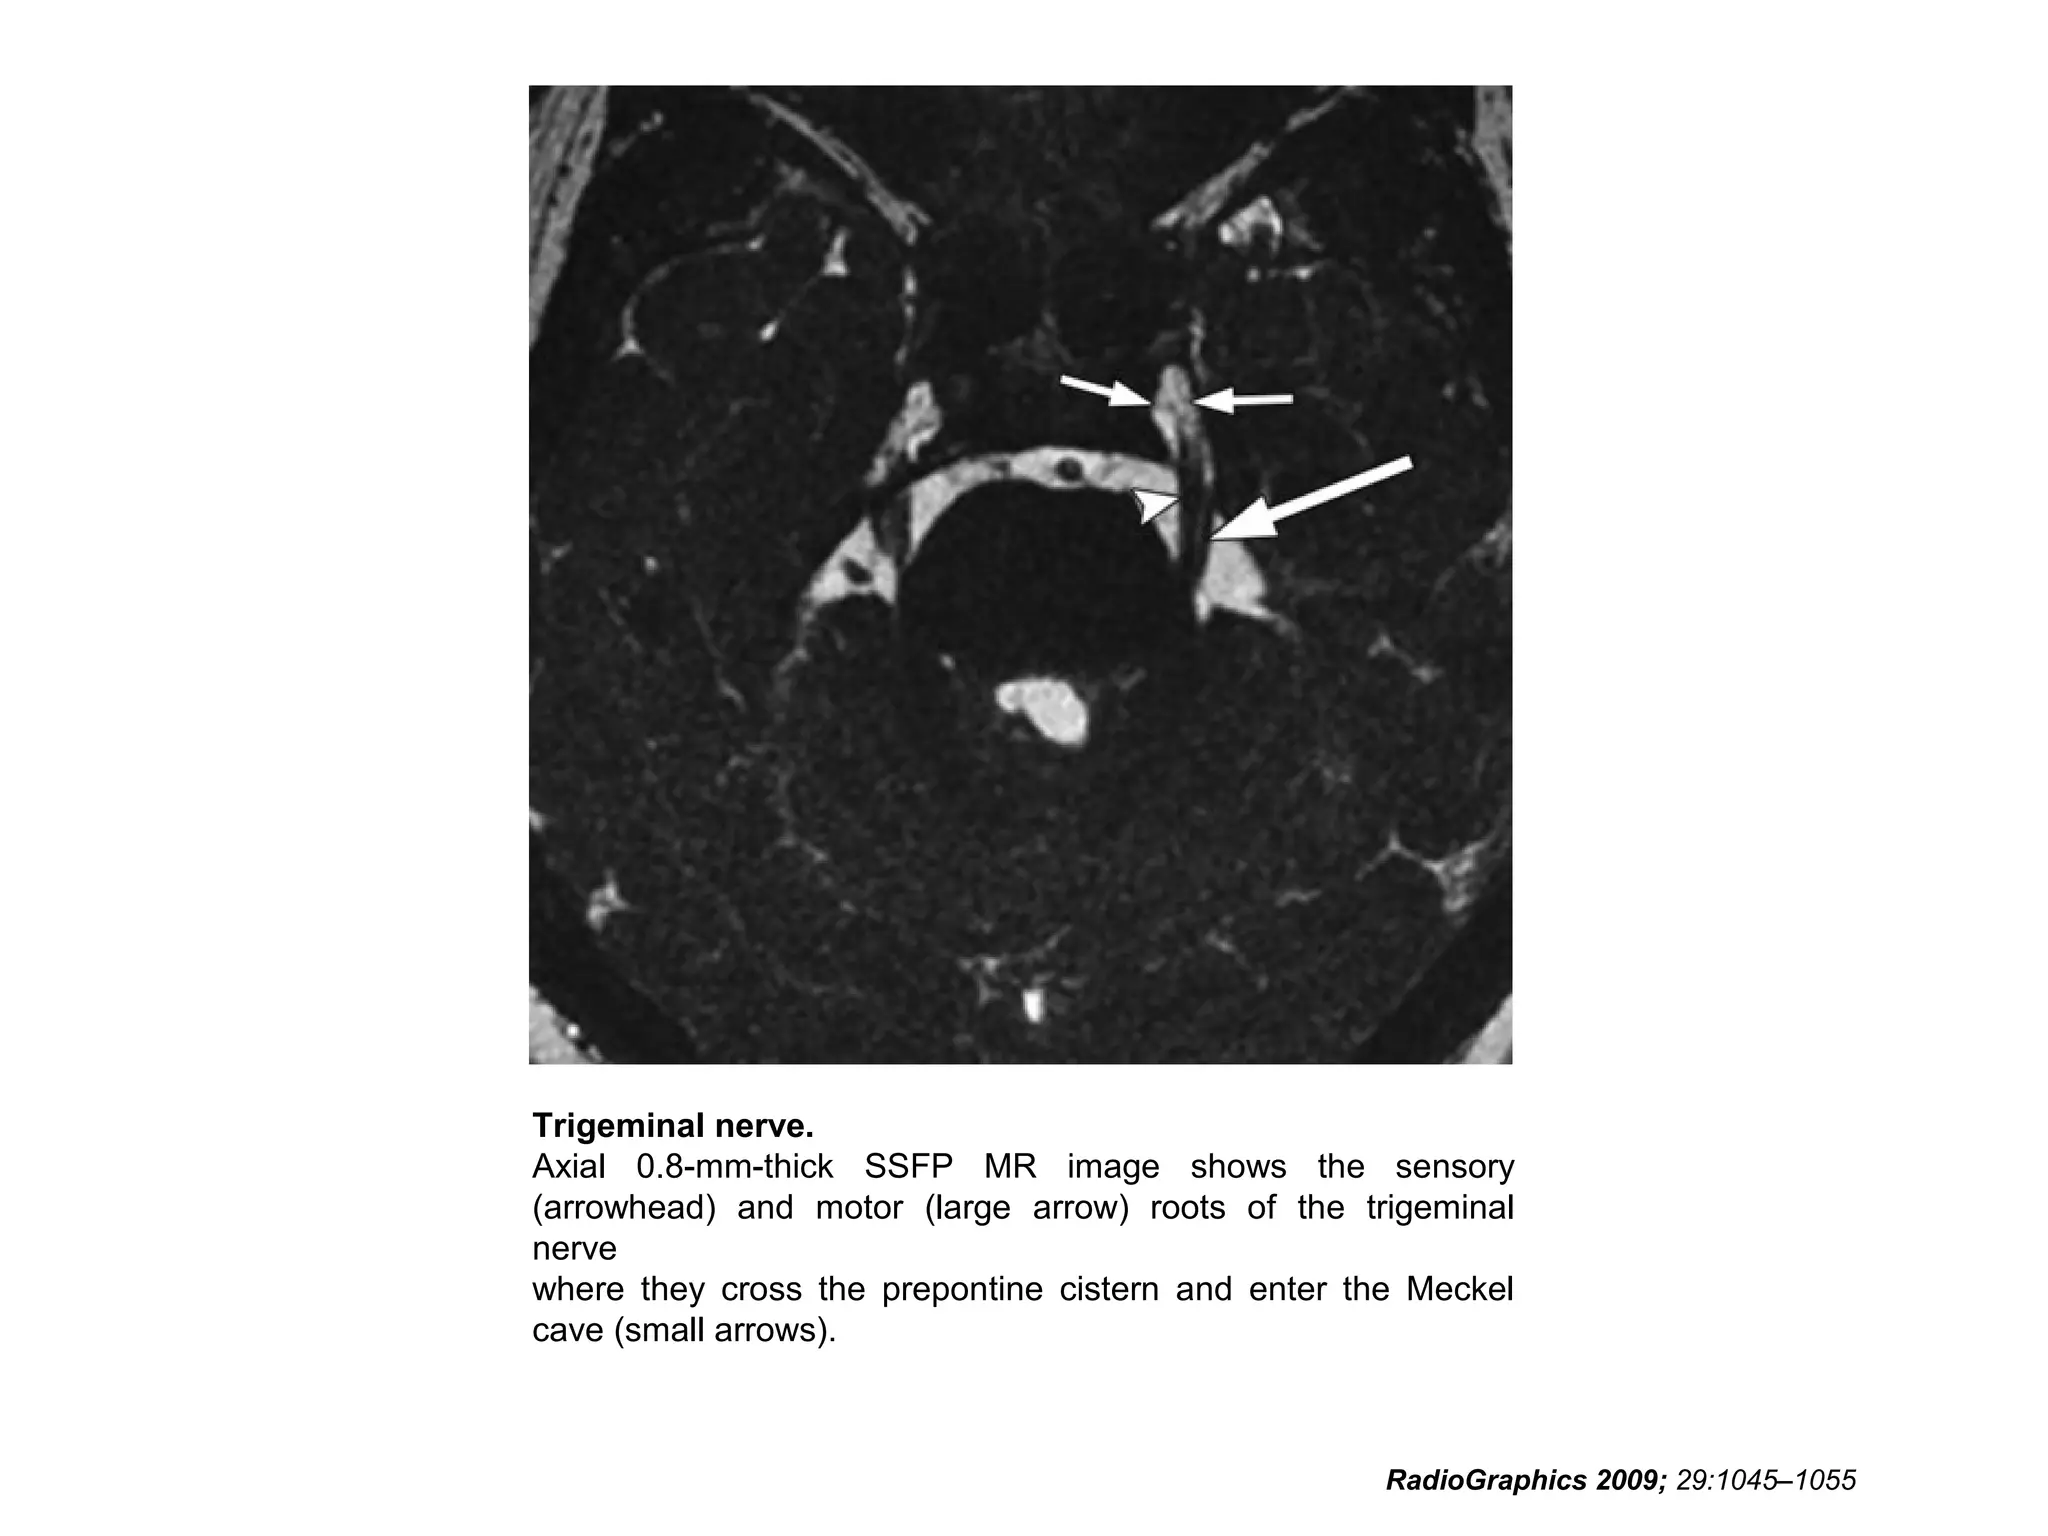

Trigeminal nerve.

Axial 0.8-mm-thick SSFP MR image shows the sensory

(arrowhead) and motor (large arrow) roots of the trigeminal

nerve

where they cross the prepontine cistern and enter the Meckel

cave (small arrows).

RadioGraphics 2009; 29:1045–1055